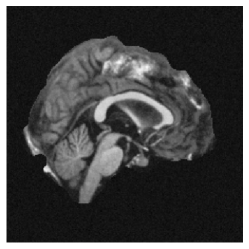

4.1 Datasets

Real-world data. We benchmarked on the OASIS-1 dataset [7], which consists of brain MRI scans of individual patients in different stages of dementia and a healthy control group. We used 5 pairs for hyperparameter tuning and the rest for evaluation. The image dimensions are voxels. Besides the intensity values, each dataset contains segmentations on regions, conducted by experts. We used the skull-stripped, affinely pre-aligned volumes provided in the dataset.

To generate the image pairs, the deformation was applied to a zero-padded reference image from the OASIS dataset, to which Gaussian noise with mean zero and standard derivation was added, resulting in a synthetic template image. Some exemplary deformations can be seen in Fig. 10.

|

coronal |

![]() |

|---|---|---|---|

axial |

central |

| reference | generated deformation | overlay |